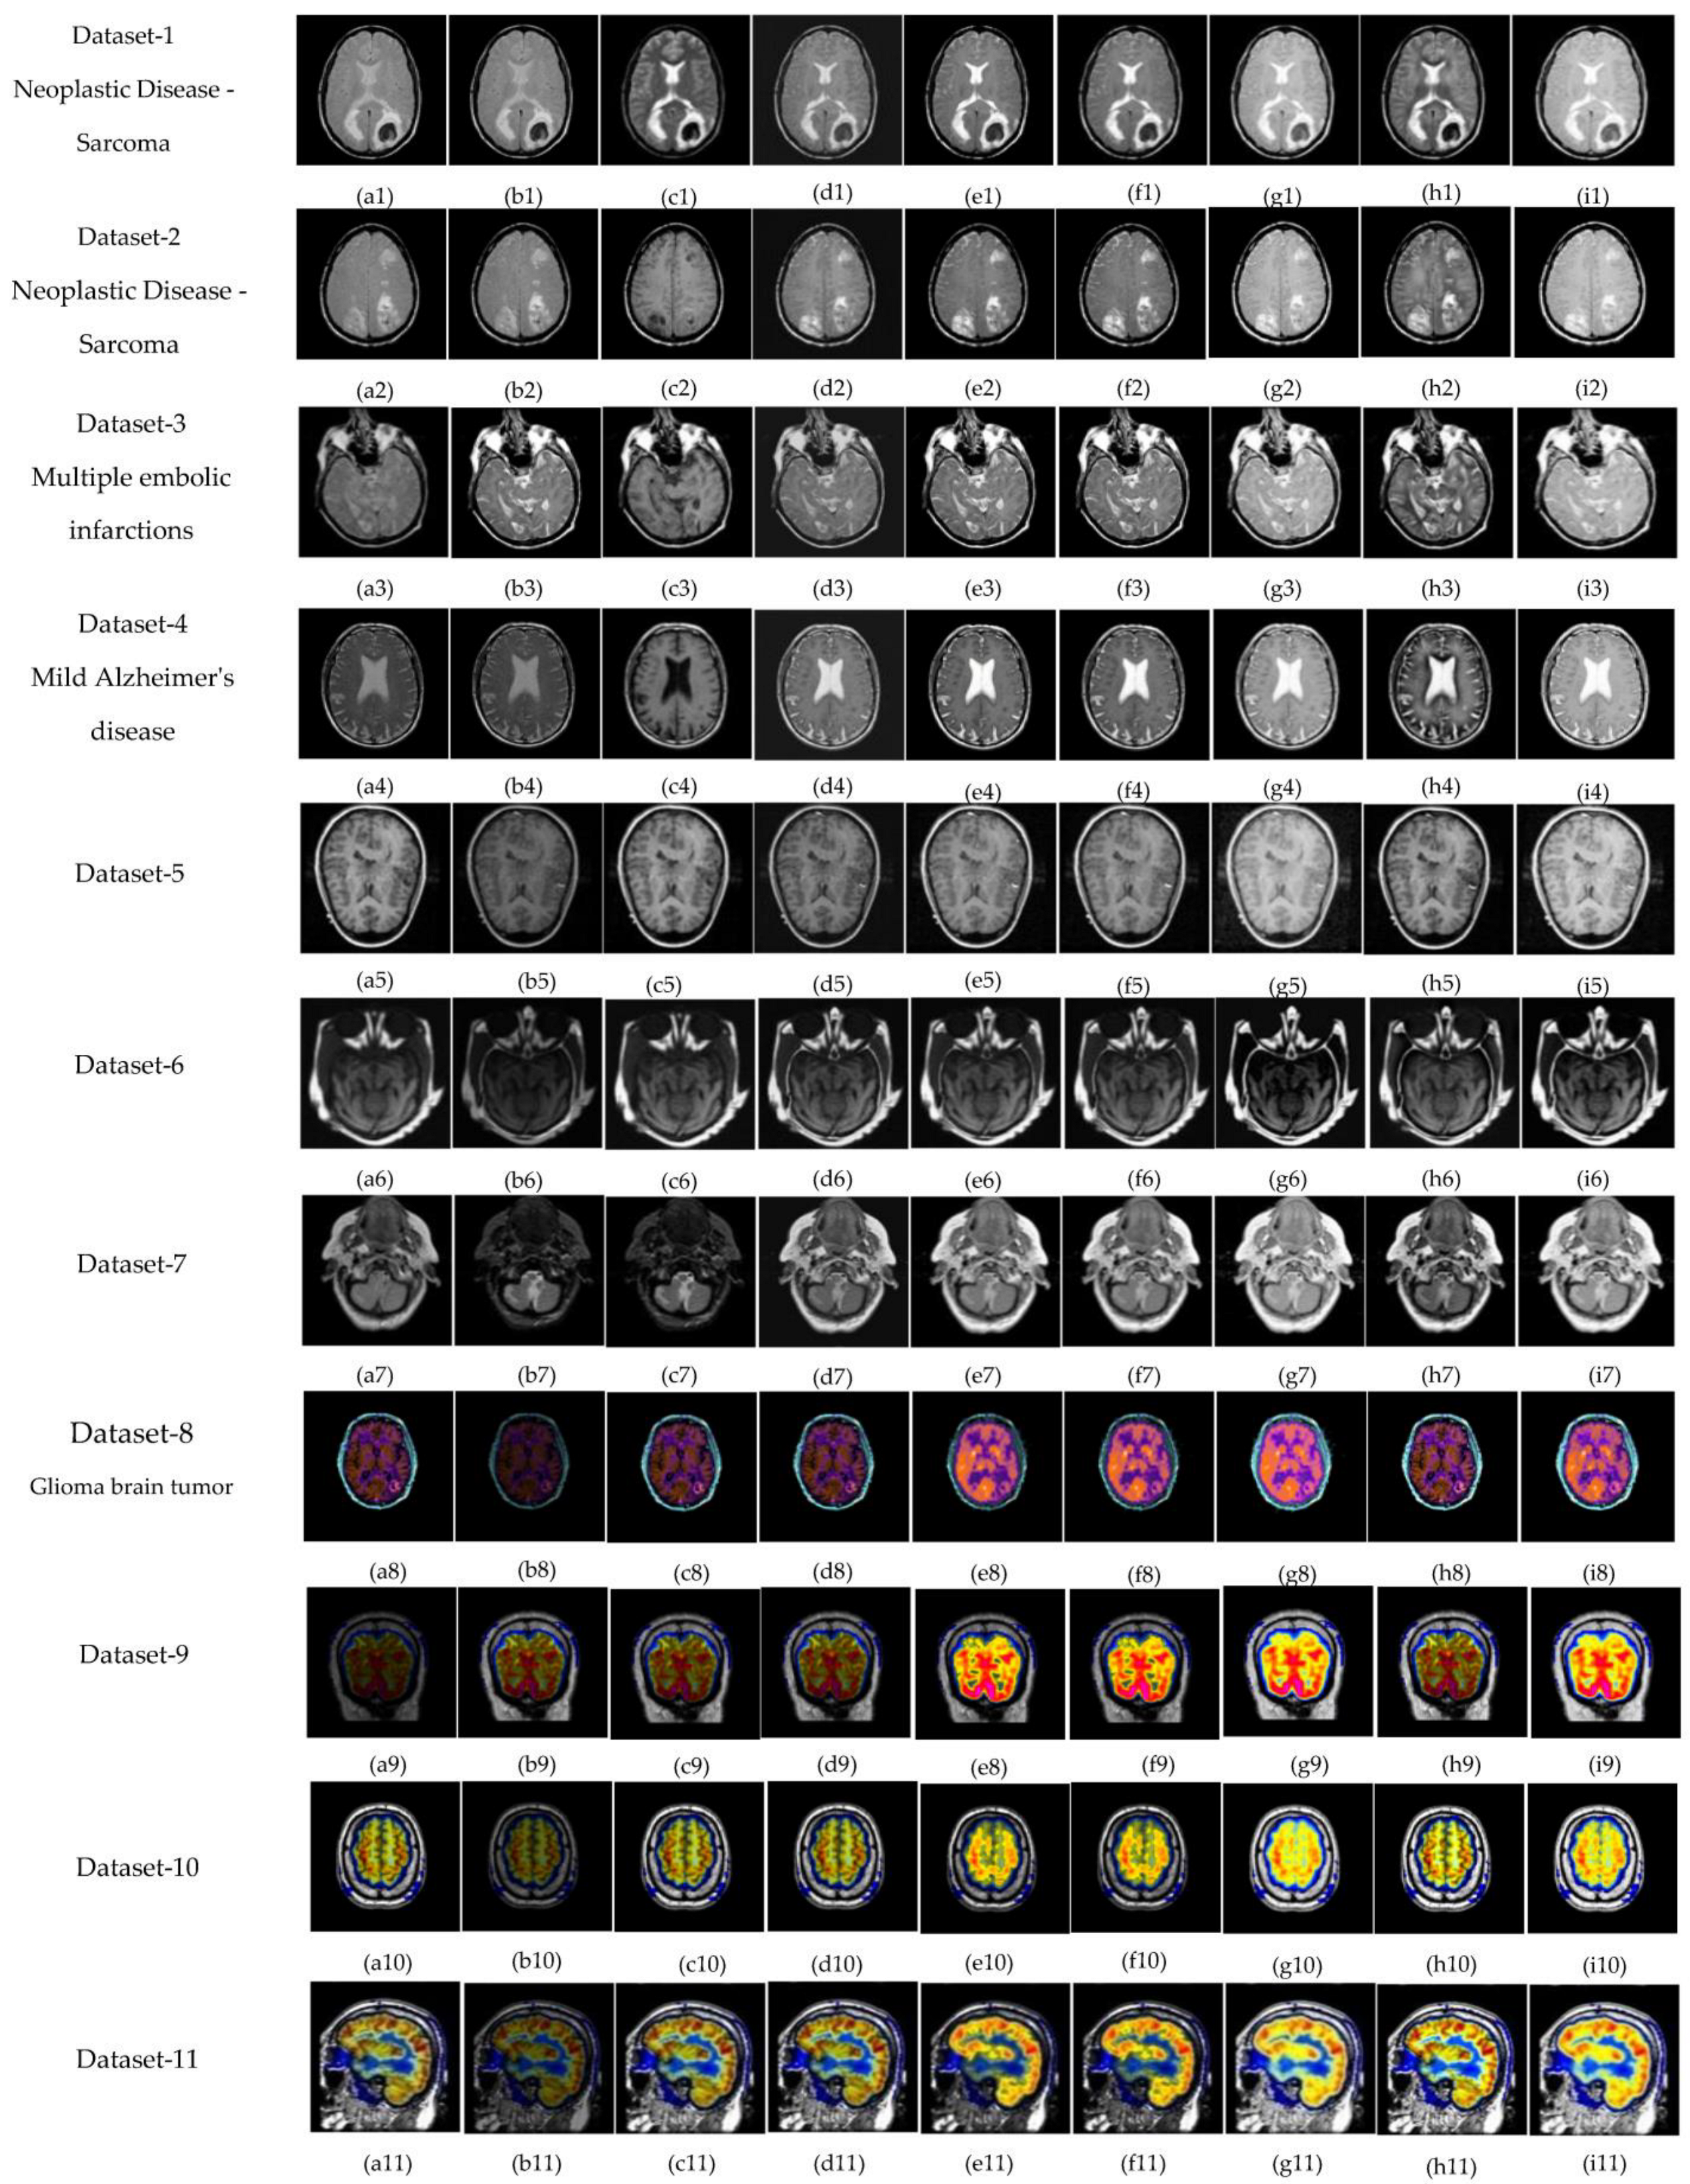

5.1. Subjective-Type Evaluation

- Brain Image. Available online: http://www.metapix.de/examples.html (accessed on 3 February 2020).

- The Whole Brain Atlas. Available online: https://www.med.harvard.edu/aanlib/home.html (accessed on 3 February 2020).